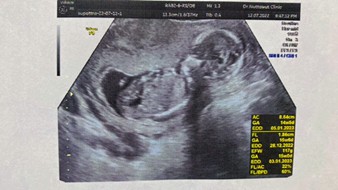

18 ธันวาค่าาา หาหมอรอบหน้าก็รู้เพศแล้ว ตอนนี้17wแล้วค่ะ